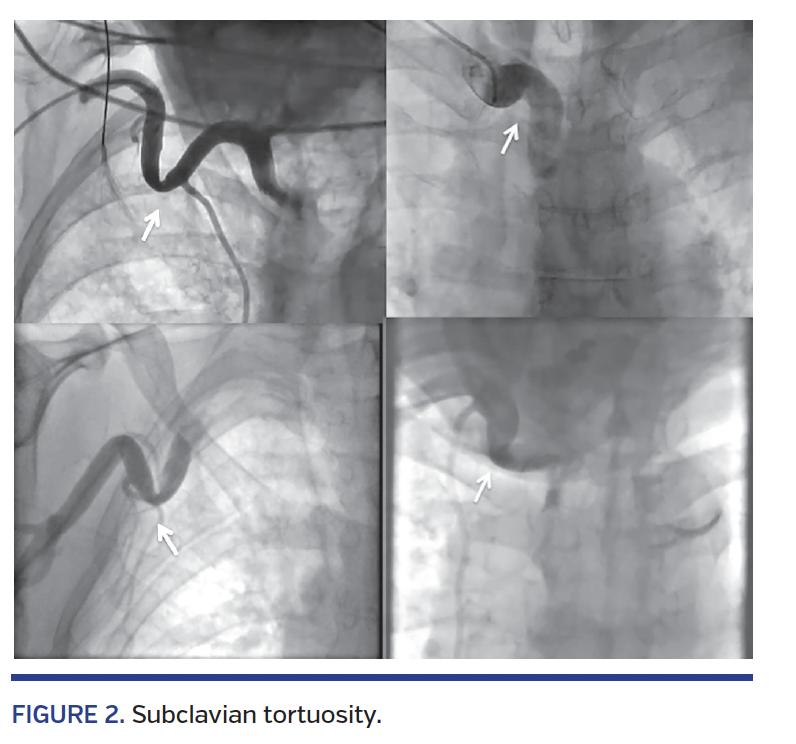

Details of the obstacles/anomalies are provided in Table 3. Radial spasm was the most commonly encountered obstacle (n = 72; 2.8%) followed by subclavian tortuosity (n = 56; 2.2%) (Figures 1 and 2). Extreme radial tortuosity and radial loops were very uncommon (<1%) (Figures 3 and 4).

Success rates with individual obstacles/anomalies are provided in Table 4. Most of the obstacles/anomalies were successfully negotiated; however, extreme radial tortuosity and radial loops had relatively lower success rates (18% and 20%, respectively). Some of the radial loop and extreme radial tortuosity cases were negotiated successfully with the use of 0.35˝ hydrophilic wires or 0.014˝ angioplasty wires (Figure 5). Subclavian tortuosity and stenosis accounted for 58 cases (2.3%) (Figures 2 and 6). Of these, 73% were successively negotiated with the use of hydrophilic wires and/or breath-holding maneuvers, which helped in straightening the loop (Figure 7). Two of the subclavian tortuosity cases were arteria lusoria (retroesophageal course of the subclavian artery); in both cases, we failed to negotiate and had to switch to femoral access.